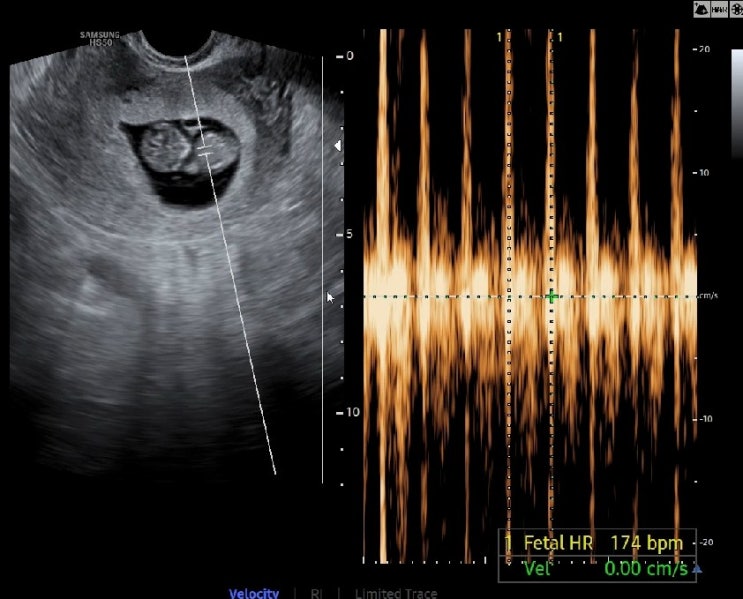

아기 초음파로 성별 추측하기 임신출산어플 스마일리더앱 각도탐정 앵글이 이용

* 본 포스팅은 스마일리더 서포터즈 활동의 일환으로 작성하였습니다. #임산부어플 #임산부어플추천 #임산...